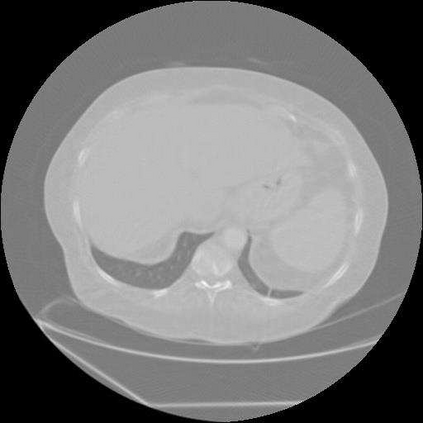

Sparse-view computed tomography (CT) is known as a widely used approach to reduce radiation dose while accelerating imaging through lowered projection views and correlated calculations. However, its severe imaging noise and streaking artifacts turn out to be a major issue in the low dose protocol. In this paper, we propose a dual-domain deep learning-based method that breaks through the limitations of currently prevailing algorithms that merely process single image slices. Since the scanned object usually contains a high degree of spatial continuity, the obtained consecutive imaging slices embody rich information that is largely unexplored. Therefore, we establish a cascade model named LS-AAE which aims to tackle the above problem. In addition, in order to adapt to the social trend of lightweight medical care, our model adopts the inverted residual with linear bottleneck in the module design to make it mobile and lightweight (reduce model parameters to one-eighth of its original) without sacrificing its performance. In our experiments, sparse sampling is conducted at intervals of 4{\deg}, 8{\deg} and 16{\deg}, which appears to be a challenging sparsity that few scholars have attempted before. Nevertheless, our method still exhibits its robustness and achieves the state-of-the-art performance by reaching the PSNR of 40.305 and the SSIM of 0.948, while ensuring high model mobility. Particularly, it still exceeds other current methods when the sampling rate is one-fourth of them, thereby demonstrating its remarkable superiority.